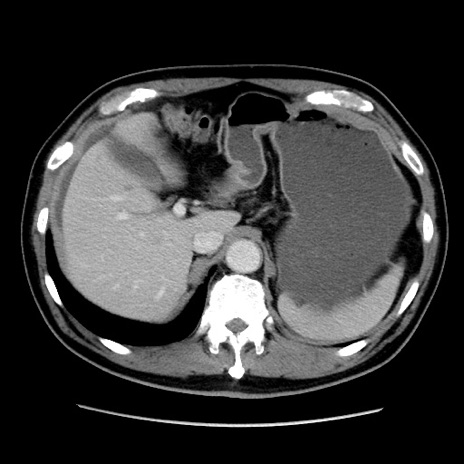

症例16(横断像)

【症例】 70歳代男性

【主訴】 腹痛、嘔吐

【現病歴】 約1ヶ月前より間欠的に腹痛と嘔吐あり、当院消化器内科を受診したところCTで多発する肝臓のLDAを指摘され、精査中であった。以降は消化器症状は安定していたが、2日前より嘔気と腹痛があり、同日より排便・排ガスが消失した。改善認めず、 本日、救急外来を受診した。

【既往歴】 大腸ポリープ切除後。

【身体所見】意識清明・会話良好、BT 36.3℃、BP 127/80mmHg、 P 80bpm、腹部:膨満あり、平坦・軟、上腹部正中および下腹部正中に圧痛あり、反跳痛なし、筋性防御なし。

【データ】WBC 7200、CRP 0.77